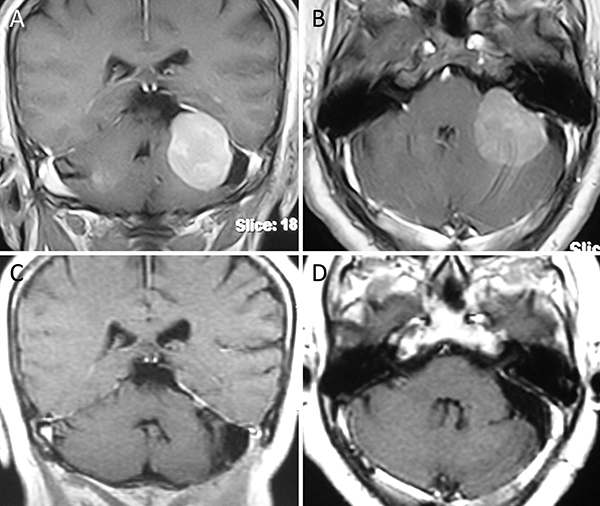

Figura 7. Meningioma de la convexidad lateral. A-B: RM preoperatoria; C-D: RM postoperatoria.